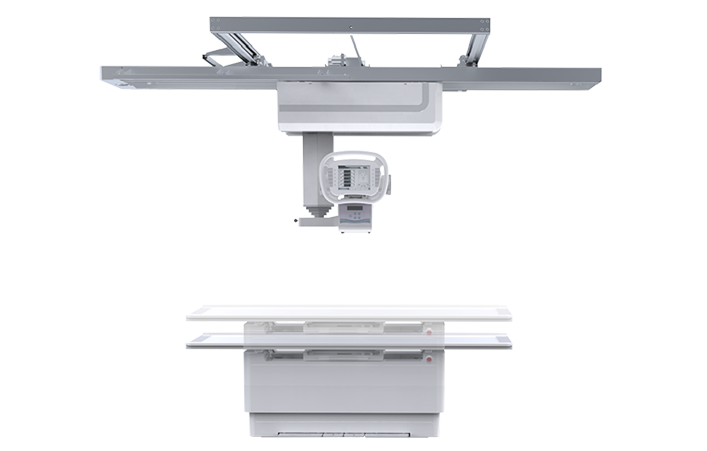

静态悬吊DR

摆位灵活 智能运动 PLD7100

采用灵活的悬吊式机架设计,配置电动升降摄影床/移动床与高品质平板探测器,实现图像与摆位的有机统一,可应用于DR摄影多种临床X线检查领域。